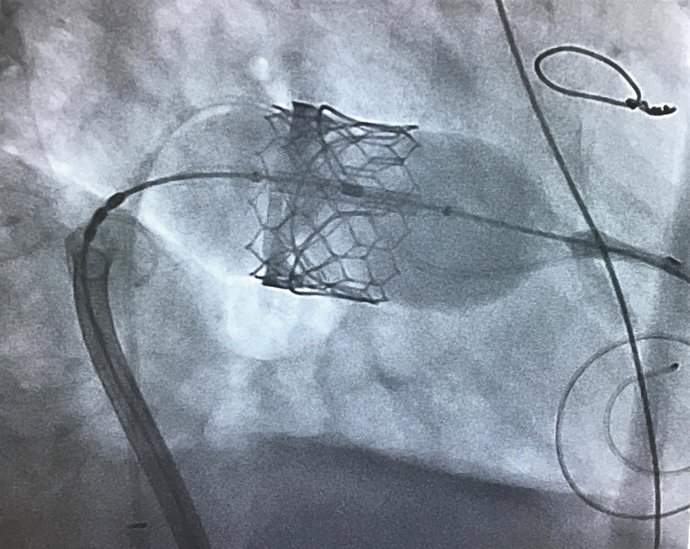

El equipo de Hemodinámica y Cardiología Intervencionista del Hospital Regional de Málaga ha llevado a cabo una compleja intervención cardiaca en la que se ha implantado una prótesis valvular mitral de forma percutánea a través de catéteres sin necesidad de cirugía abierta, lo que ha redundado en una más rápida y efectiva recuperación de la paciente a la que se le practicó, minimizando, además, los riesgos.

Conocida como 'valve in valve mitral', esta técnica ha evitado que la paciente se someta a una cirugía a corazón abierto con circulación extracorpórea. La mujer había sido intervenida hace años mediante un reemplazo valvular mitral con una cirugía cardíaca convencional, a corazón abierto, y se le implantó una prótesis biológica, pero esta se había deteriorado y había empeorado la calidad de vida de la paciente.

Lejos de las indicaciones iniciales, para las que era necesaria una operación a corazón abierto, el equipo del Hospital Regional sólo necesitó hacer una pequeña incisión para canalizar la vena femoral a nivel de la ingle. De este modo, avanzaron un catéter con la nueva válvula a través del tabique interauricular y la posicionaron dentro de la válvula antigua degenerada para, finalmente, liberarla una vez alcanzada la posición definitiva. La recuperación de la paciente fue satisfactoria, con una estancia reducida en UCI y fue dada de alta a su domicilio en un tiempo menor al necesario en una cirugía convencional.